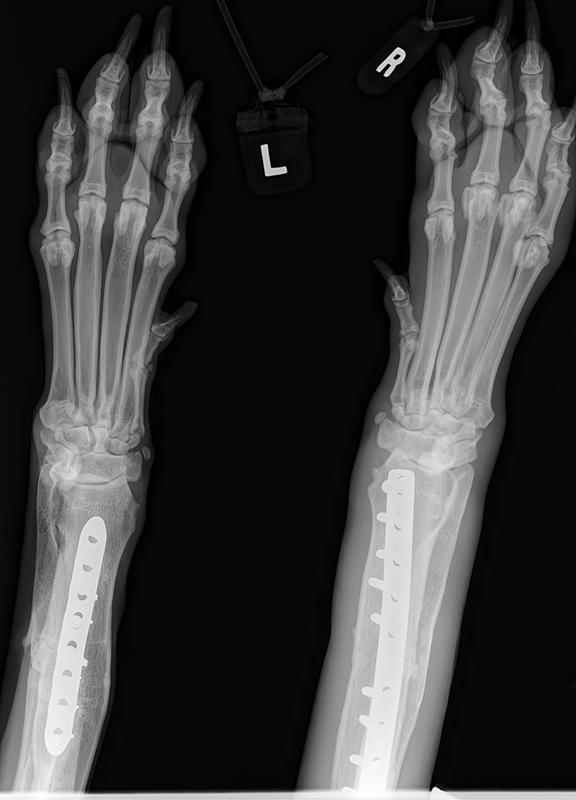

His surgery to remove the implant on his left front leg after a sudden rejection/infection with the plate screws was on September 24th. This is his fourth leg surgery. He had two surgeries on his front legs which were deformed when he first arrived to BHRR and then now he has had to have two more surgeries due to reacting to the Implants.

Surgery started late yet all is done and The Mavie, our true Iron Man has his ‘new’ leg!

BHRR’s Mavie is having that front left leg implant removed. He developed a sudden infection and rejection of the plate/screws.

He has his surgery scheduled to remove that left front leg implant on Tuesday November 24th with his wonderful ortho specialist. He had a sudden rejection/infection to that left implant recently and now that the Baytril(almost $600 for 16 days worth of treatment) has worked its magic on the infection, he is ‘good to go’ for surgery!

It does appear that I may well be correct that after 2 years and four months plus from first having the original leg surgery, he is now rejecting this implant. He had this leg first operated on in July 2013. frown emoticon

BHRR’s Mavie, for those who are not familiar with his journey has had two surgeries on his front legs, ended up reacting to the fixator on the left front leg, then last November rejected the implant in the right front leg and now, is having symptoms very similar on the left front leg.

As many are aware, in November of 2014, BHRR’s Maverick, had a violent aggressive reaction to the implant in his right front leg and had to spend several months on strong antibiotics, had to have an emergency surgery to remove the plate/screws and was treated for a terrible abscess from reacting to the implant. His ortho specialist even cultured the implant to see what may be brewing on it…..

How it started with his right leg is how his left leg is now ‘appearing’ to be.